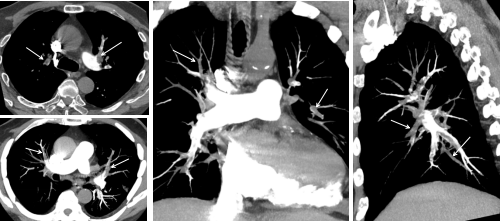

利用CT扫描技术,通过静脉注射像“染色剂”一样的造影剂使肺动脉系统显影,犹如为血管“点亮导航”。它能清晰呈现肺动脉形态、血流是否通畅,是否有堵塞物(血栓、癌栓、脂肪、羊水等),为肺栓塞诊断提供确凿依据。

肺动脉栓塞VR(图中白箭头→:栓塞部位)

两肺多发肺动脉栓塞(图中白箭头→:栓塞部位)